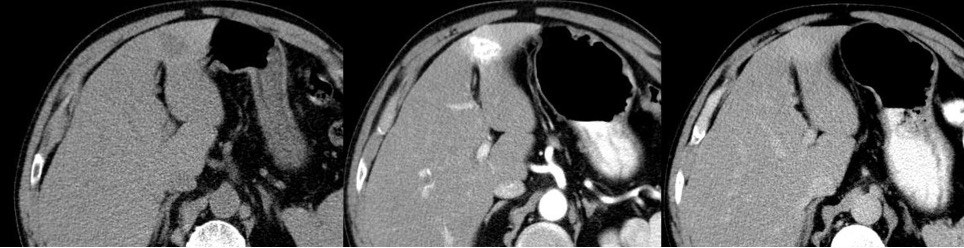

Aspetto TC

- Formazione ipodensa, a margini netti, dotata di spiccato enhancement arterioso (cicatrice centrale ipodensa), con isodensità in fase tardiva (cicatrice centrale iperdensa).